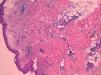

Case ReportThe patient is a 70 years old male with no history of interest, who had recurrent episodes of 2 weeks with high fever, leukocytosis, and erythematous papules and plaques on the extremities, with dense neutrophilic infiltrates in the biopsy (Fig. 1). The patient had asymmetric oligoarthritis affecting the wrist and knees. Analytically, there was an elevated sedimentation rate (ESR), leukocytosis, and anemia. Episodes were treated with glucocorticoids at 0.5mg/kg, with little response. The disease became chronic and recurrent. Indomethacin was prescribed a dose of 150mg/day and potassium iodide was added, without improvement. In parallel, the patient was diagnosed with a type 1 RABE after the study of persistent anemia. We performed multiple red blood cells transfusions.